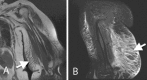

Stewart-Treves syndrome is a rare cutaneous angiosarcoma with a poor prognosis. Physicians must be aware of this lethal syndrome, especially in patients who have been treated for breast cancer with radiation and lymph-node dissection (such as the case reported here). Patients who develop unexplained enlarging plaques of coalescing purple papules should have immediate biopsy for early diagnosis of Stewart-Treves syndrome. MRI, along with PET/CT, can help evaluate the extent of disease and help with treatment strategies.